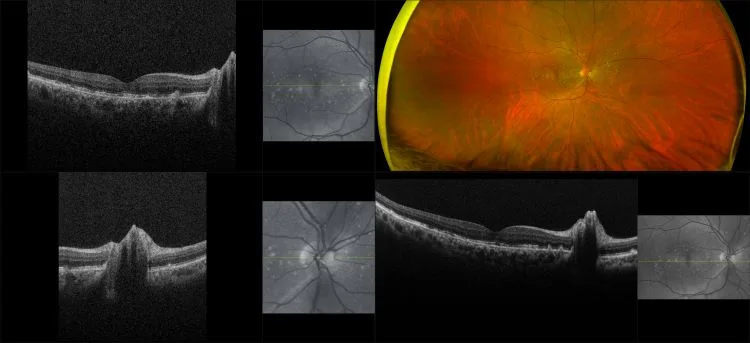

MonacoPro - Dry AMD, RG, OCT

Age-related macular degeneration is found in two forms 1. Dry early form. 2. Wet (serous leakage or whole blood). Early dry form typically has drusen (usually around 63u) and RPE degeneration and only needs periodic follow-ups, intermediate dry form has large drusen (>125u) and RPE degeneration and proliferation which requires examinations every 3 to 6 months depending on the severity of the presentation.